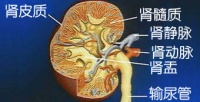

肾脏位于胸腰之间两侧的肾窝内,由于背部坚强的纵行肌肉与腹腔脏器的固定,一般不会过多

地移位。但因肾周脂肪囊下方是一个潜在的疏松的间隙,因此当腹压降低时,肾脏就可能向下移位造成肾下垂。